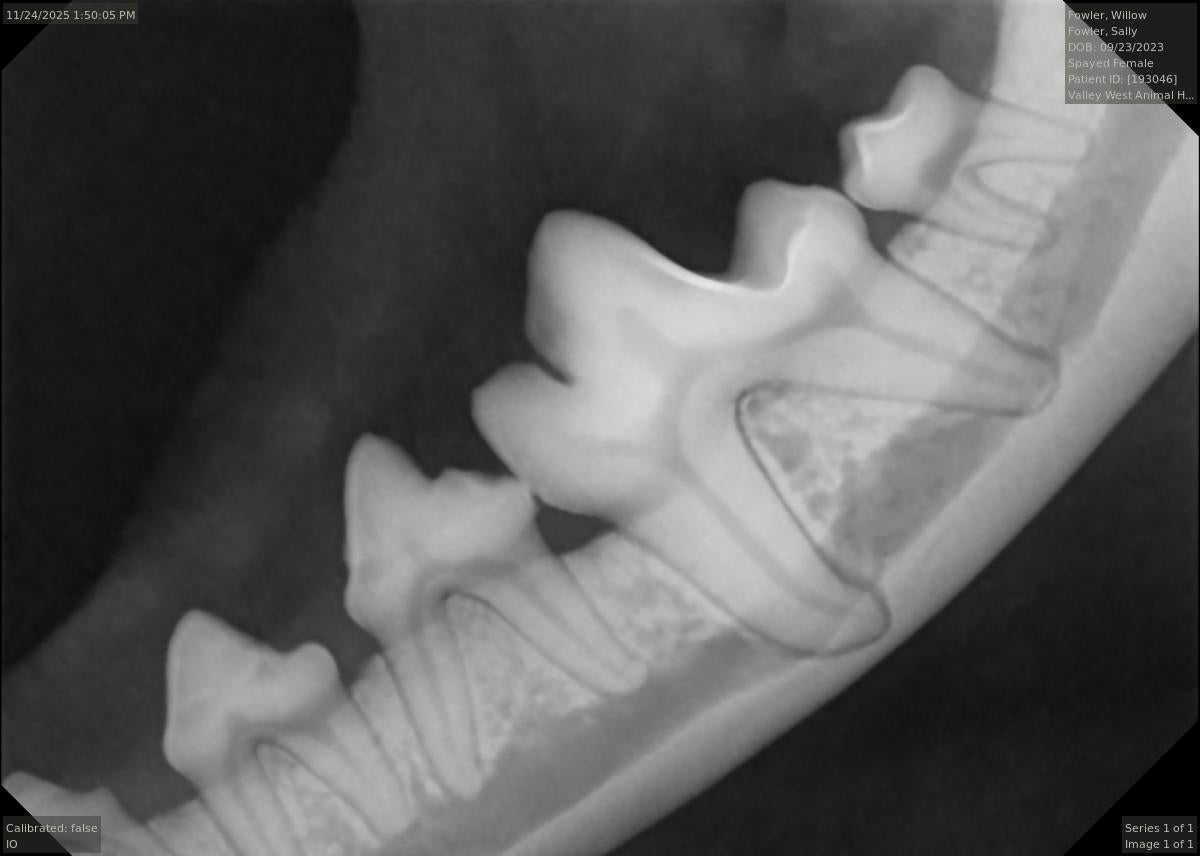

Tooth extraction is another very common procedure. It is the goal of our practice for your pet to retain as many teeth as possible. However, sometimes extraction is the only option to relieve pain or ensure that periodontal disease does not advance. If not extracted, many times a diseased tooth can compromise the surrounding tissue and neighboring teeth. If caught early, there are more treatment options available for periodontal disease.

Catching dental problems in the early stages can greatly help your pet in the long run. Contact our practice right away if your pet experiences any of the following:

- Yellowish brown crust of tartar around the gum line

- Missing, loose or broken teeth